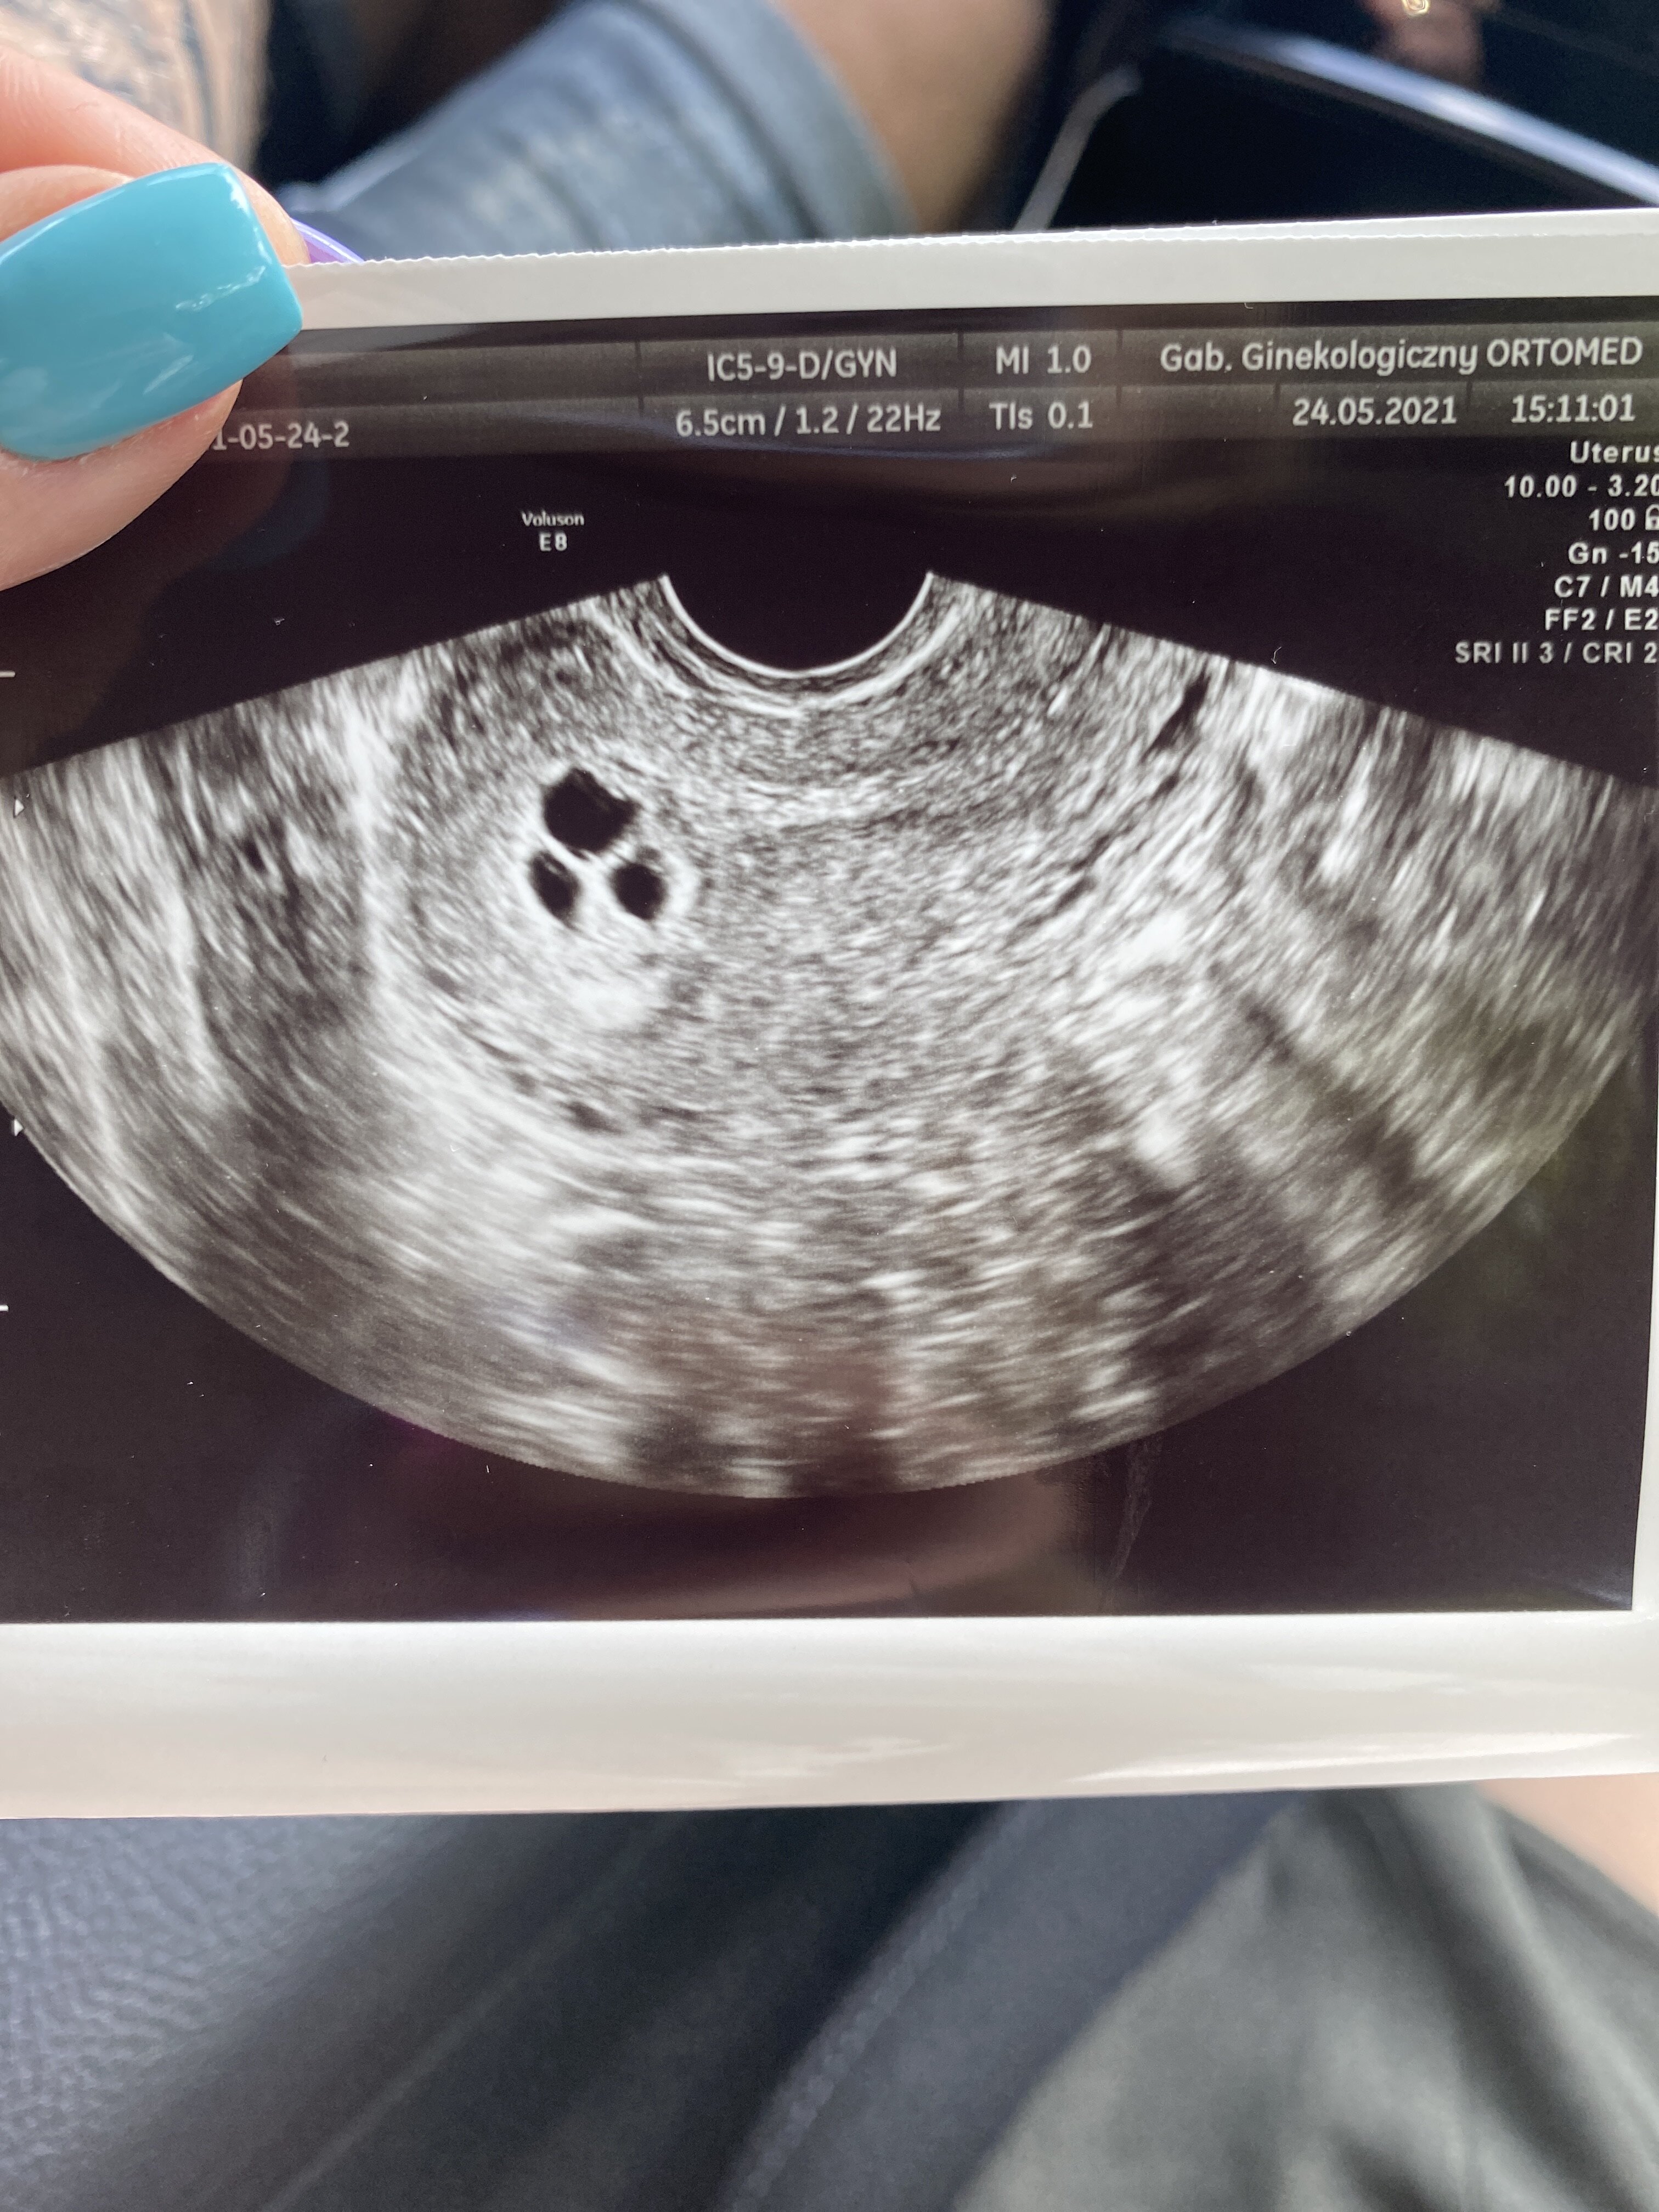

Dziewczyny jestem po wizycie i jestem w totalnym szoku tak samo jak mój lekarz . Nie wiem co mam wgl myśleć . Według OM 7 tydzień ale UGG się nie pokrywa na tym etapie już. Są trzy pecherzyki z ciałkiem żółtym bez zarodka . Jestem w szoku . Powiedział mi ze ciężko mu to zinterpretować bo na codzień się to nie zdążą . Może być tak ze pojawia się 3 zarodki , 2 , 1 lub wgl nic z tego nie bedzie . Nie wiem co mam powiedzieć nawet . Wizyta za tydzień .